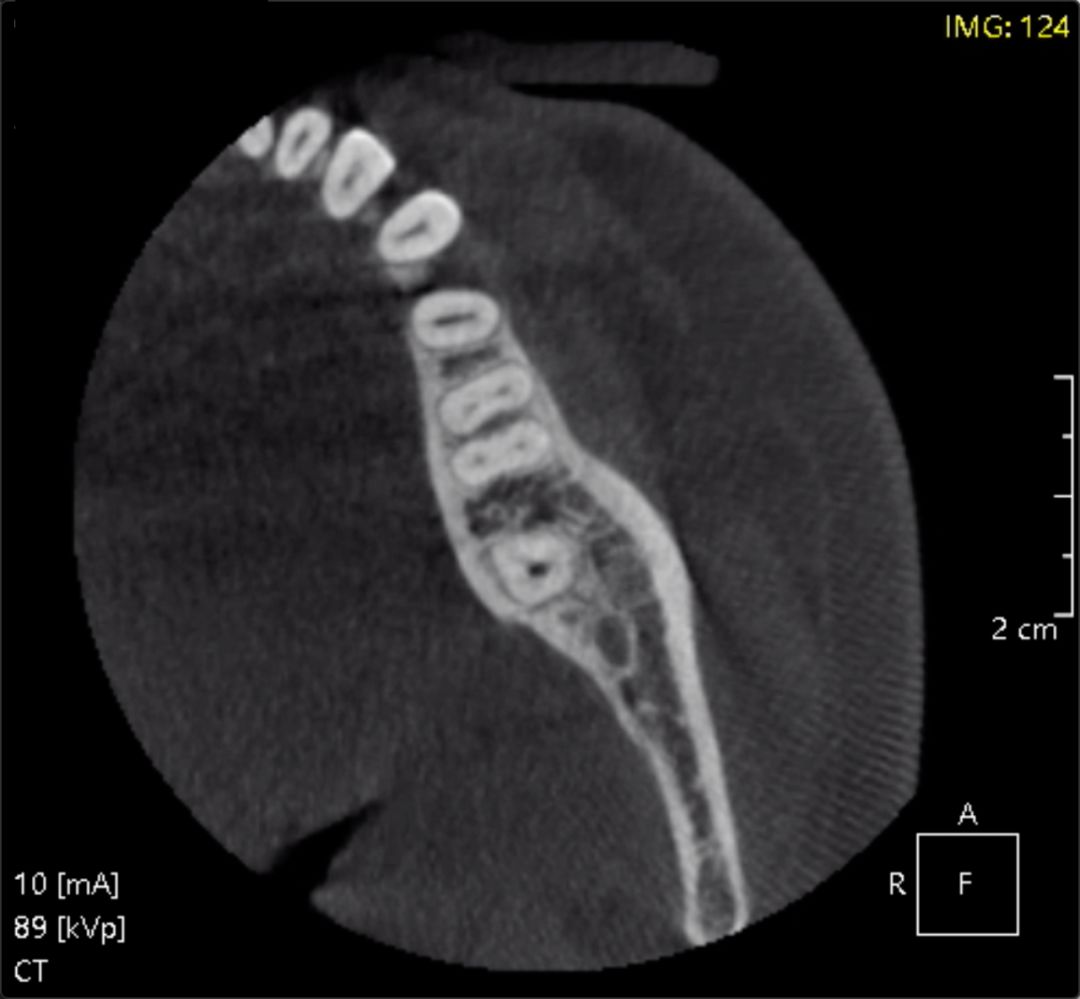

作为一个不见棺材不落泪的壮士,直到生死存亡之际我才去了医院。在医生最终决定做根管治疗之后,要先去拍个片子,看看牙根是什么样子。你以为的牙根可能是这种可爱的样子,但它们实际上可能是各种放荡不羁的样子,不太好对付。

各种奇怪的牙根丨视频截图

一个不羁的牙片丨视频截图